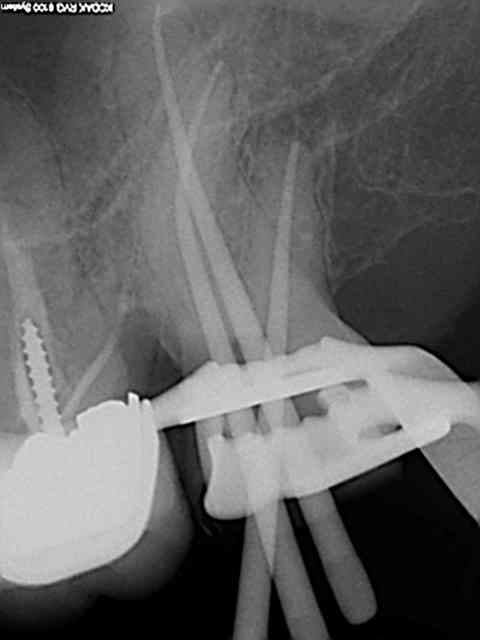

Exemple concret, de ce samedi (exceptionnellement au boulot car c'est un pote qui travaille sur Paris et qui a une semaine de vacances), j'en ai tous les jours.

la première radio date de 2011 issue d'un status inutile selon la sécu. Suspicion de reprise en mésial sous l'onlay de 27, noté sur le dossier à surveiller. Le patient appelle pour douleurs lancinantes spontanées la semaine dernière en haut au fond et à gauche exacerbées par le froid.

Diagnostic clair net et précis et par téléphone en plus : ca n'est pas du au tt merdique de la 26. Ce qui est confirmé in situ par la radio numéro 2 prise le jour meme de l'endo.

Comme à mon habitude je m'excuse d'avoir irradié le patient copieusement ( à raison de 70 kv et 0,099 s par cliché) plutot qu'un seul cliché argentique en fin de tt ( 70 kv aussi mais 1,3 s d'exposition lui) développé en fin de journée comme ca a du etre le cas pour le tt de 26 ( et m... encore raté).

Je sais pas moi mais le résultat parle de lui meme ( putain de mv2 que j'ai réussi à choper dans un 2 eme temps une fois les autres obturés)

Taille empreinte provisoire dans la foulée , l'avantage de la gutta chaude.

Vous préférez quoi dans votre bouche ? une seule radio et un tt endo comme la 26 ou 6 clichés et mon tt endo de 27 ?